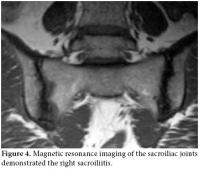

The laboratory testing results were as follows: rheumatoid factor (RF), 11 U/ml (0-20); erythrocyte sedimentation rate (ESR), 67 mm/h (0-20); C-reactive protein (CRP), 85.43 mg/dl (0-5); and the total blood count, urea, creatinine, and electrolyte values were normal. The hepatitis, antinuclear antibody (ANA) along with the Salmonella and Brucella titers were all negative. The purified protein derivative (PPD) skin and pathergy tests were also negative. No findings were detected on the throat culture or in the direct fecal and parasite examinations. HLA-B27 was negative. A chest X-ray showed the hilar plenitude (figure 1). High resolution computed tomography (HRCT) revealed the bilateral hilar lymphadenopathy (LAP) and multiple mediastinal LAP along with several nodules adjacent to several irregular nodules (the largest was 2.5x1.5 cm) in both lungs, which was compatible with stage II sarcoidosis (figure 2). Using a gallium-67 whole body screening method, an activity enhancement in both the hilar and mediastinal regions was consistent with lymph node involvement. The diagnosis of sarcoidosis was confirmed by a bronchoscopic biopsy. A pelvis radiograph and sacroiliac magnetic resonance imaging (MRI) were performed, and the results were normal. The patient was diagnosed as having Löfgren's syndrome, which is a clinical subtype of acute sarcoidosis involving acute arthritis, LAP, and EN. Steroid treatment was administered, and recovery was observed on the arthritis of the right ankle and EN after two weeks. On follow-up, the clinical and laboratory findings (ESR, 35 mm/h; CRP, 7.89 mg/dl) had improved dramatically. During the clinic management of the patient at three months, the patient complained about hip pain, so a radiograph of the sacroiliac joint was performed again. Sclerosis was shown in the inferior regions of both sacroiliac joints on the sacroiliac X-ray (figure 3), and right sacroiliitis was found on the MRI of the sacroiliac joints (figure 4). The complaints of the patient were address by administering nonsteroidal antiinflammatory drugs (NSAIDs), and the patient continued to be followed up.